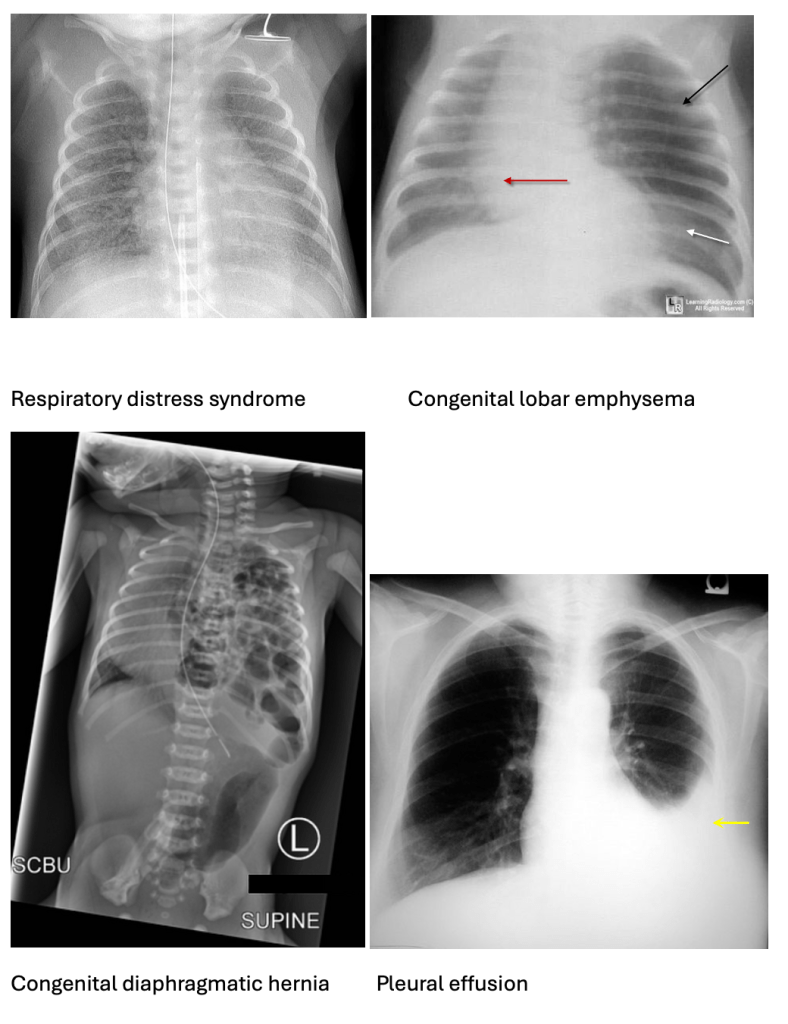

A) is incorrect as respiratory distress syndrome (RDS) seen in preterm infants due to surfactant deficiency. X-rays show ground-glass opacities.

B) is incorrect as congenital diaphragmatic hernia (CDH) presents with severe respiratory distress, scaphoid abdomen, and X-rays show bowel loops in the thorax.

C) is incorrect because meconium aspiration syndrome (MAS) occurs in term/post-term infants with meconium-stained amniotic fluid. X-rays show patchy infiltrates and areas of overinflation.

E) is incorrect as Pulmonary Hypoplasia is associated with CDH (congenital diaphragmatic hernia) or prolonged oligohydramnios. X-rays show small, bell shaped, underdeveloped lungs.

B) is incorrect as Transient Tachypnoea of the Newborn (TTN) is caused by delayed clearance of foetal lung fluid. It presents with mild respiratory distress and normal surfactant levels. X-rays show fluid in the fissures, not ground-glass opacities. TTN would be likely in a term baby born by C-section without labour, presenting with tachypnoea but resolving in 24-48 hours.

C) is incorrect as Meconium Aspiration Syndrome (MAS) occurs when the infant inhales meconium-stained amniotic fluid (amniotic fluid with faeces), often in term or post-term babies. X-rays show patchy infiltrates, not uniform ground-glass.

D) is incorrect as Congenital Diaphragmatic Hernia (CDH) involves abdominal organs herniating into the thoracic cavity, impairing lung development (pulmonary hypoplasia). X-rays show bowel loops in the chest.

E) is incorrect as Pulmonary Hypoplasia is the underdevelopment of lung tissue and is often secondary to CDH or oligohydramnios. It leads to severe respiratory failure, but X-rays show small lung volumes and bell-shaped lungs rather than classic RDS findings.

A) is incorrect as ground-glass appearance: Indicates RDS- respiratory distress syndrome.

C) is incorrect as hyperinflated left upper lobe is seen in CLE – congenital lobar emphysema.

D) is incorrect as bowel loops in the thorax suggests CDH- congenital diaphragmatic hernia.

E) is incorrect as pleural effusion is fluid in the pleural cavity, not related to TEF.